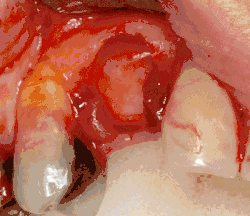

An incision is made across the area and the flap of gingiva is opened to show the bone of the jaw.

An incision is made across the gingiva, and the flap of tissue is reflected to show the bone of the jaw.

1. Soft tissue reflection: An incision is made over the crest of bone, splitting the thicker attached gingiva roughly in half so that the final implant will have a thick band of tissue around it. The edges of tissue, each referred to as a flap, are pushed back to expose the bone. Flapless surgery is an alternate technique, where a small punch of tissue (the diameter of the implant) is removed for implant placement rather than raising flaps.